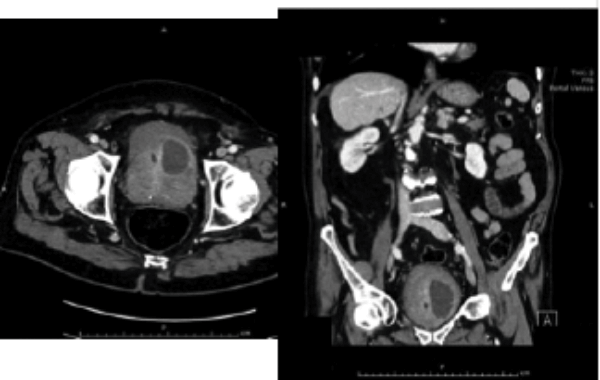

An 82-year-old diabetic man with a long-term catheter presented to the Emergency Department with rigors and non-specific abdominal pain. He had an elevated white cell count (WCC) and C-reactive protein (CRP). An abdominal and pelvic CT scan was arranged. Selected CT images are shown below:

There is a peripherally enhancing collection in the left anterosuperior aspect of the prostate. Diagnosis: left sided prostatic abscess.